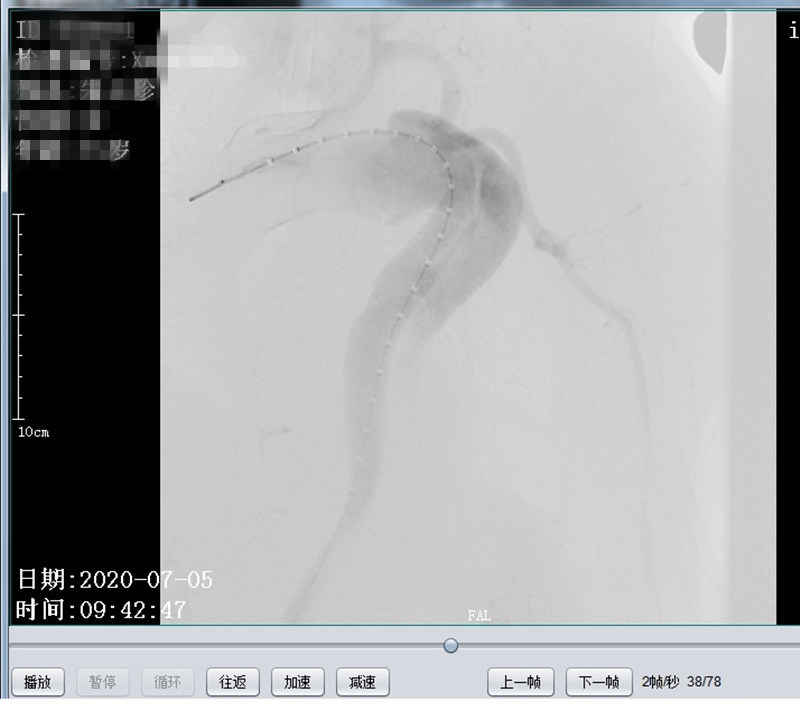

术前造影,原支架近端可见造影剂外溢,原支架远端胸主动脉呈瘤样扩张

术中开窗后定位

术后造影,主动脉弓处破口消失,左颈总动脉显示可,左锁骨下动脉显示良好,胸主动脉显示良好,原扩张段消失,支架周围未见明显内漏。